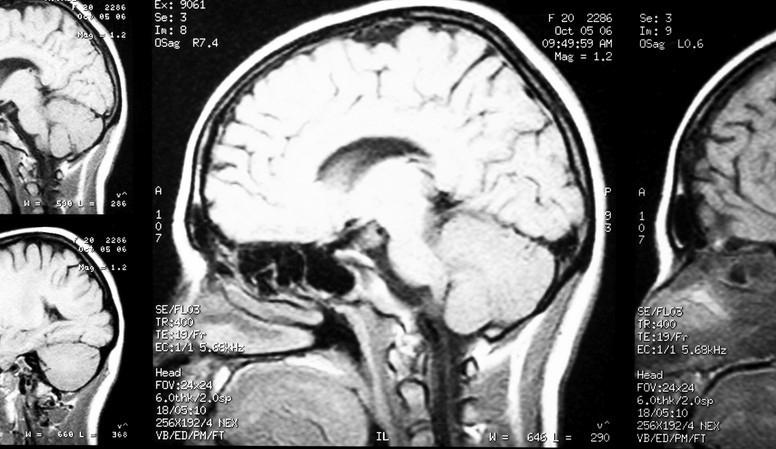

Çoğu zaman diş tedavileri sırasında ortaya çıkan uyuşukluk ve hafif rahatsızlıklar normal karşılanır. Ancak, bir hastanın bu semptomlar uzayıp yaygınlaştığında, altta yatan ciddi bir sorunun işareti olabileceği önem kazanır. McInerny’nin yaşadığı durum, tedavi sonrası ortaya çıkan nadir bir nörolojik rahatsızlık olan hemifasiyal spazm ile ilgiliydi.

İlk başta endişelenmeden diş hekimine gitti, ancak zamanla belirtiler şiddetlenip günlük yaşamını etkiler hale geldi. Sağ yüzünün bir tarafında hissedilen ani kas seğirmeleri, göz kapağında istemsiz kapanma ve yüzün diğer bölümlerinde oluşan garip hisler önemli bir uyarı niteliğindeydi.